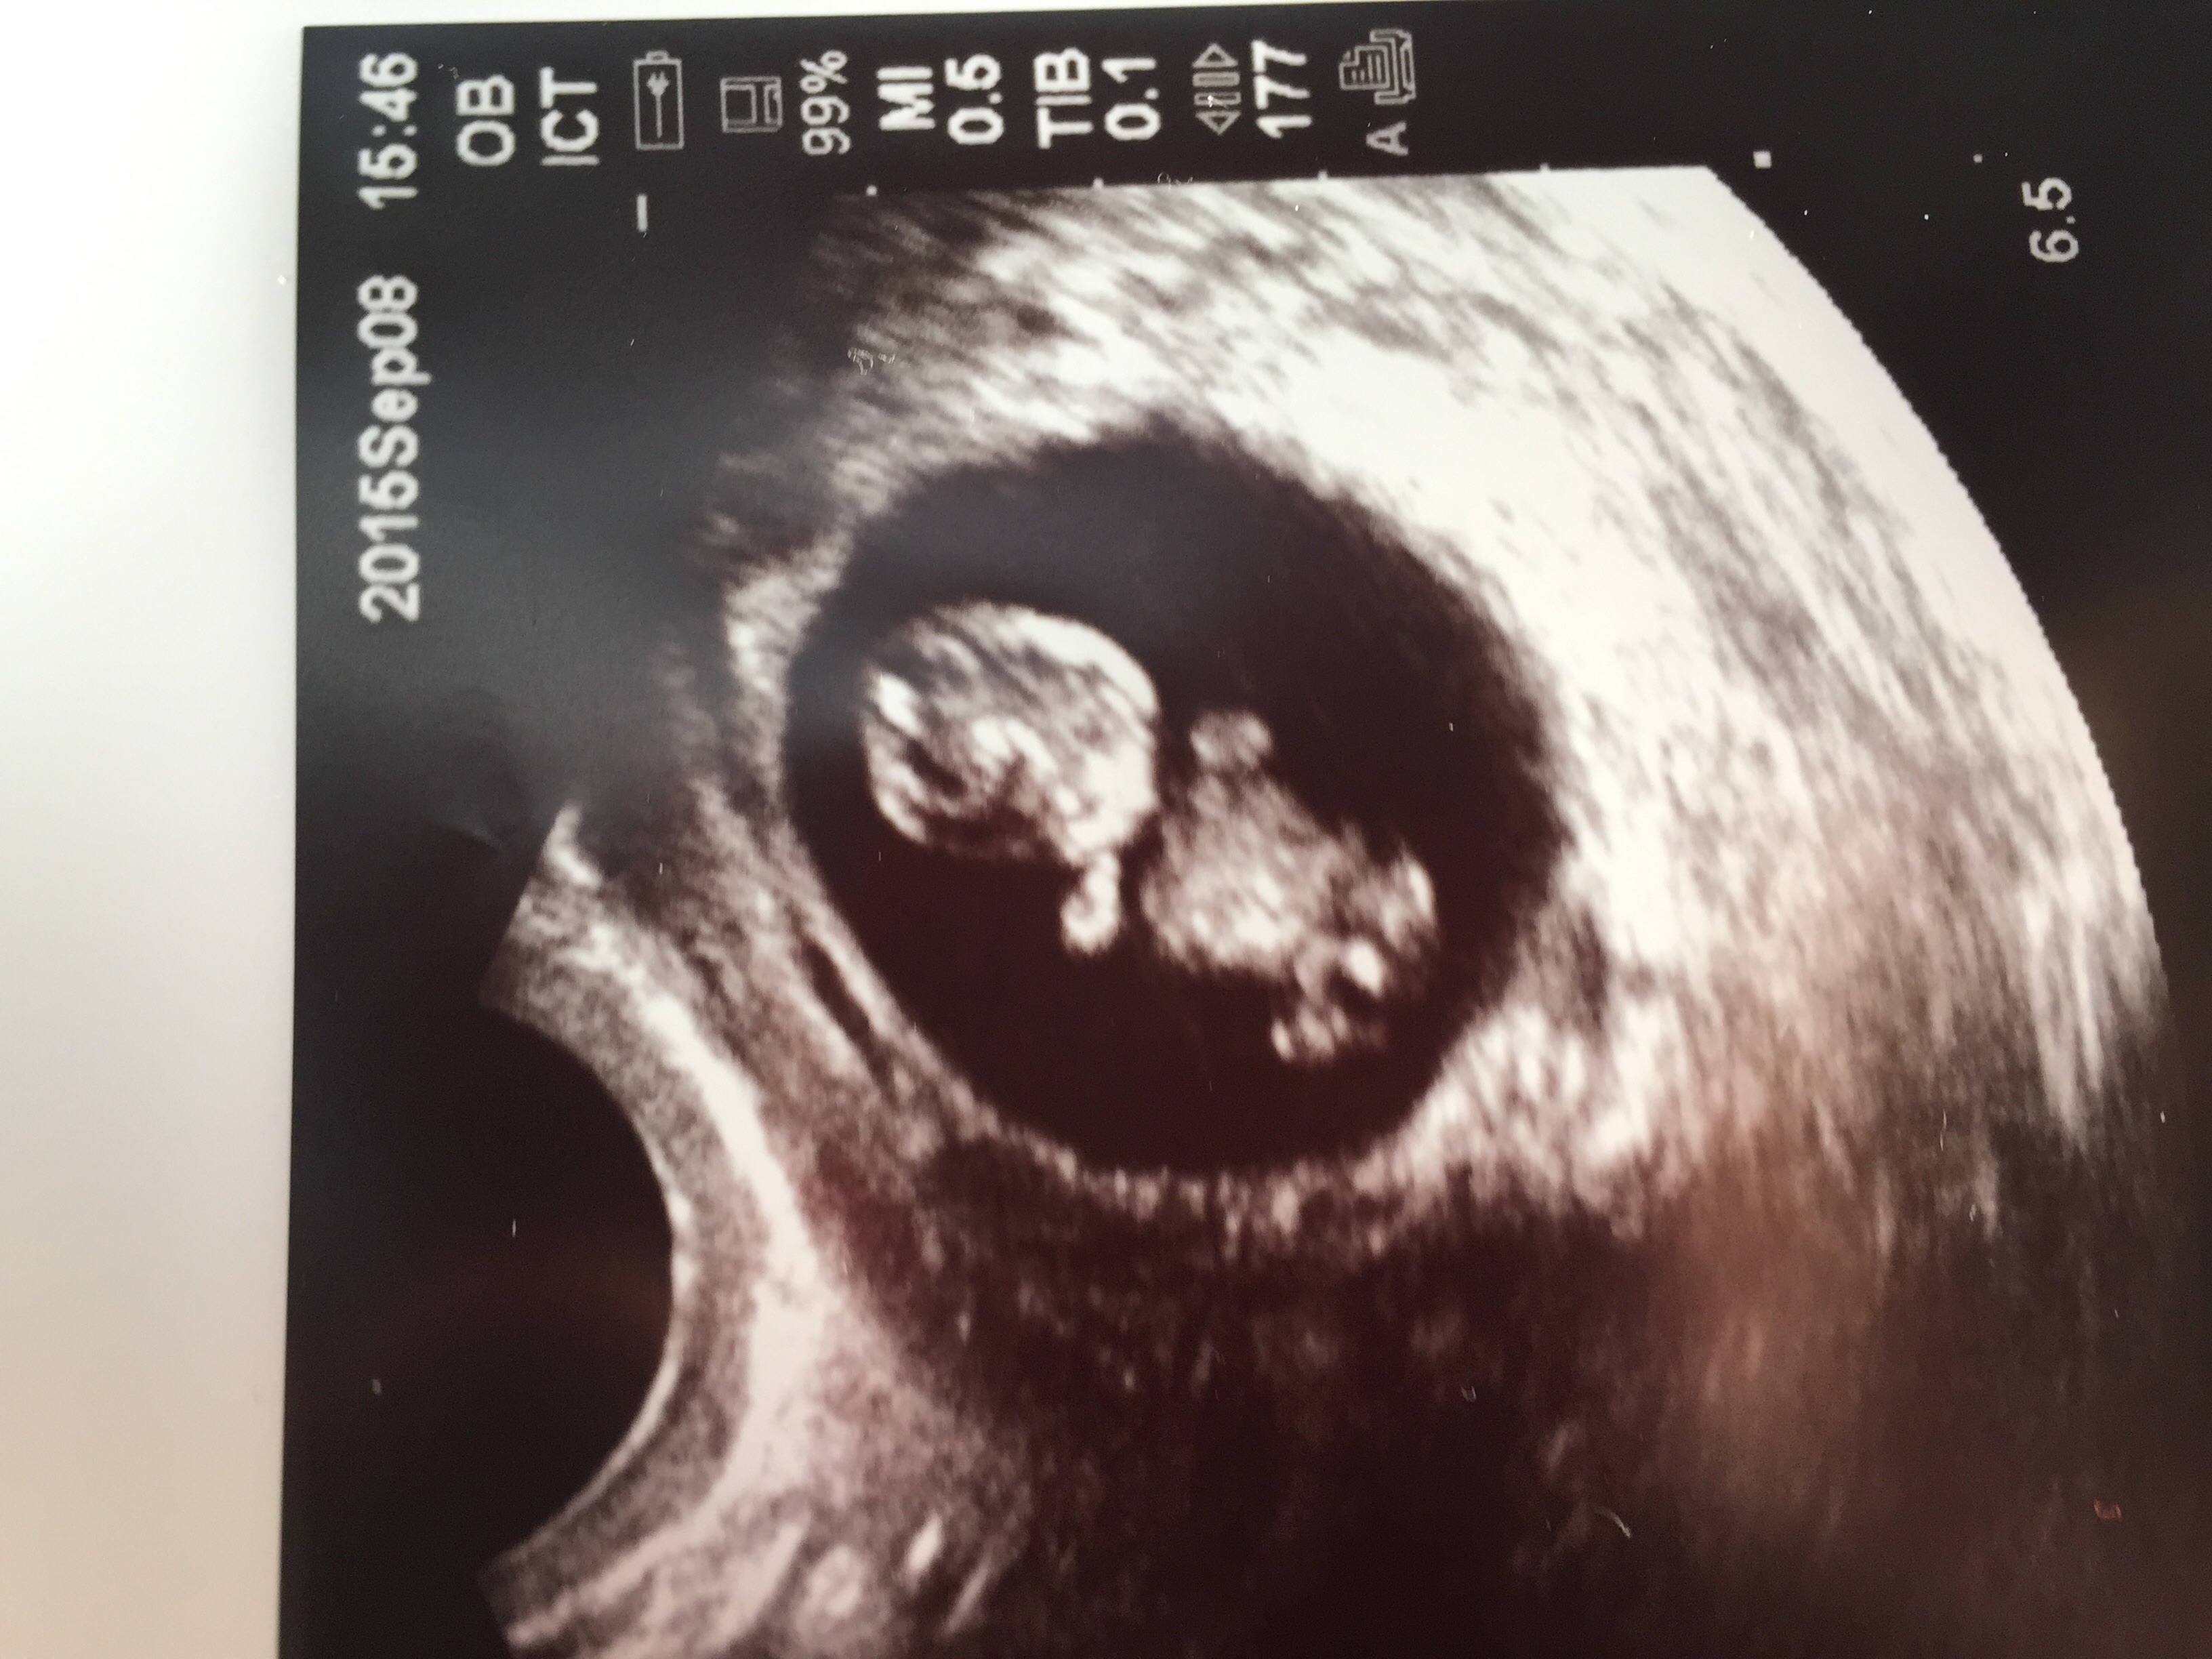

Here we are!!! I've been so excited to post this. My rainbow baby at 8w2d. Measured exactly as we thought with 165bpm. Baby looks a bit like a Lego character so I'm picturing "everything is awesome" playing on repeat as baby grows!!! Due April 13!